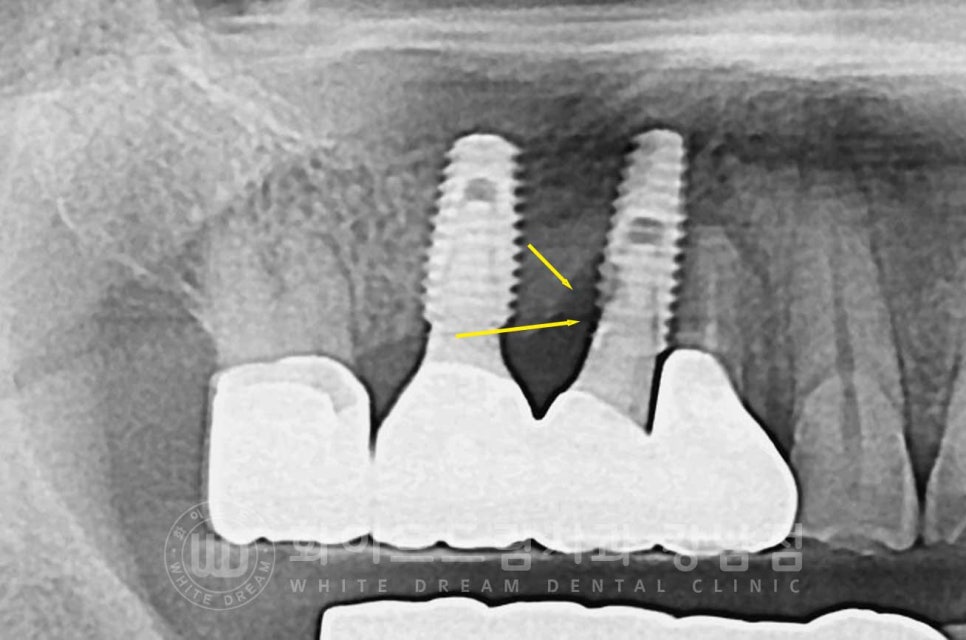

임플란트 찢어짐, 조금 생소하시죠?

인공 나사가 찢어진 상태를 임플란트 찢어짐이라고 하는데요.

임플란트가 찢어지면 찢어진 주위로 세균이 모여 염증이 발생하고

염증으로 잇몸뼈가 녹게 되는 악순환이 발생하고 흔들림으로 정상적인 기능을 할 수 없기에

이 찢어진 임플란트는 제거 후 재식립을 진행해야 한답니다.